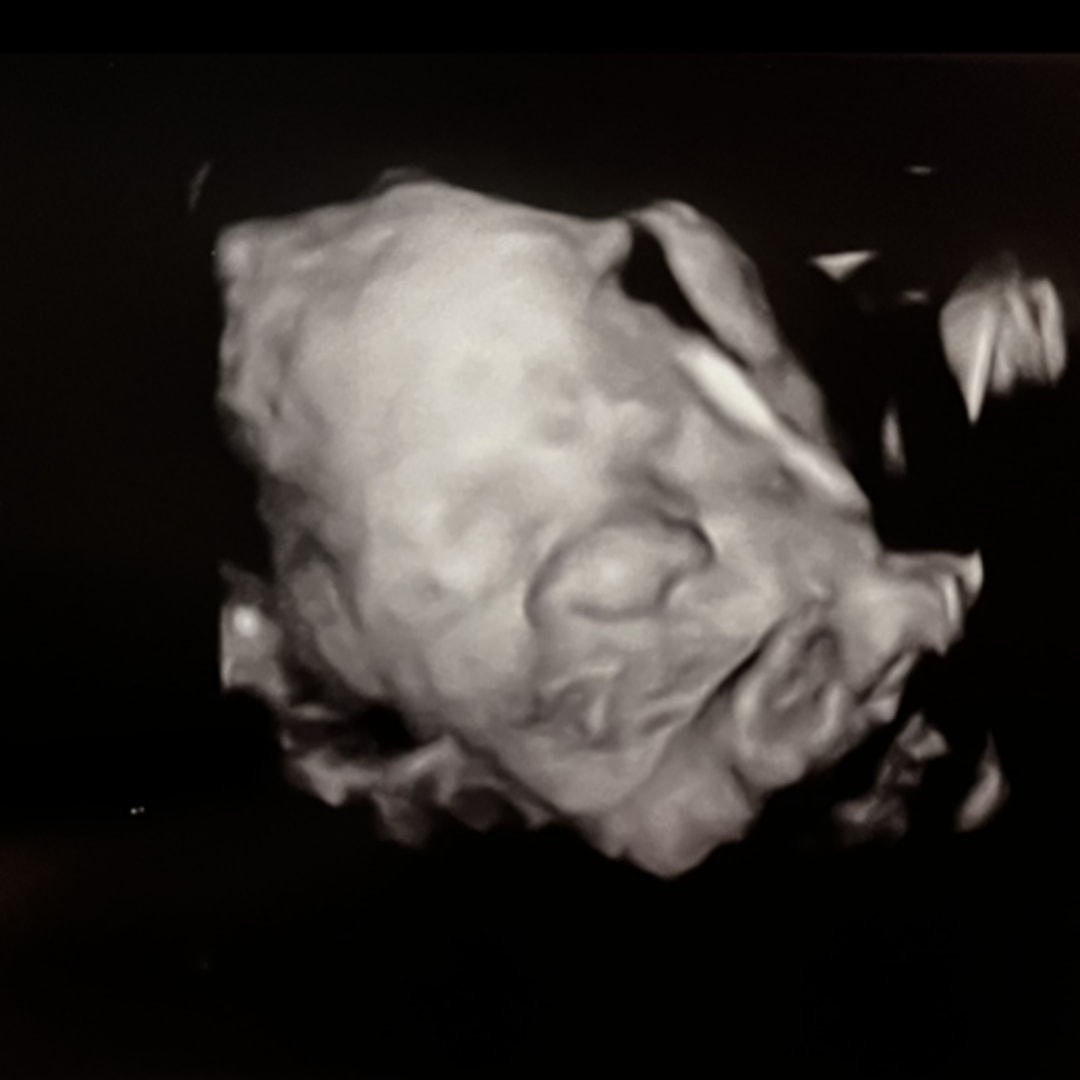

Hello everyone! Thank you for viewing our registry! ☺️ We are ready to welcome Madeline Jones Brewer in March 2026! 🩷

Pearhead "Love at First Sight" Sonogram Frame

babylist Icon

$12.99

target Icon

amazon Icon

from $9.99

I purchased this